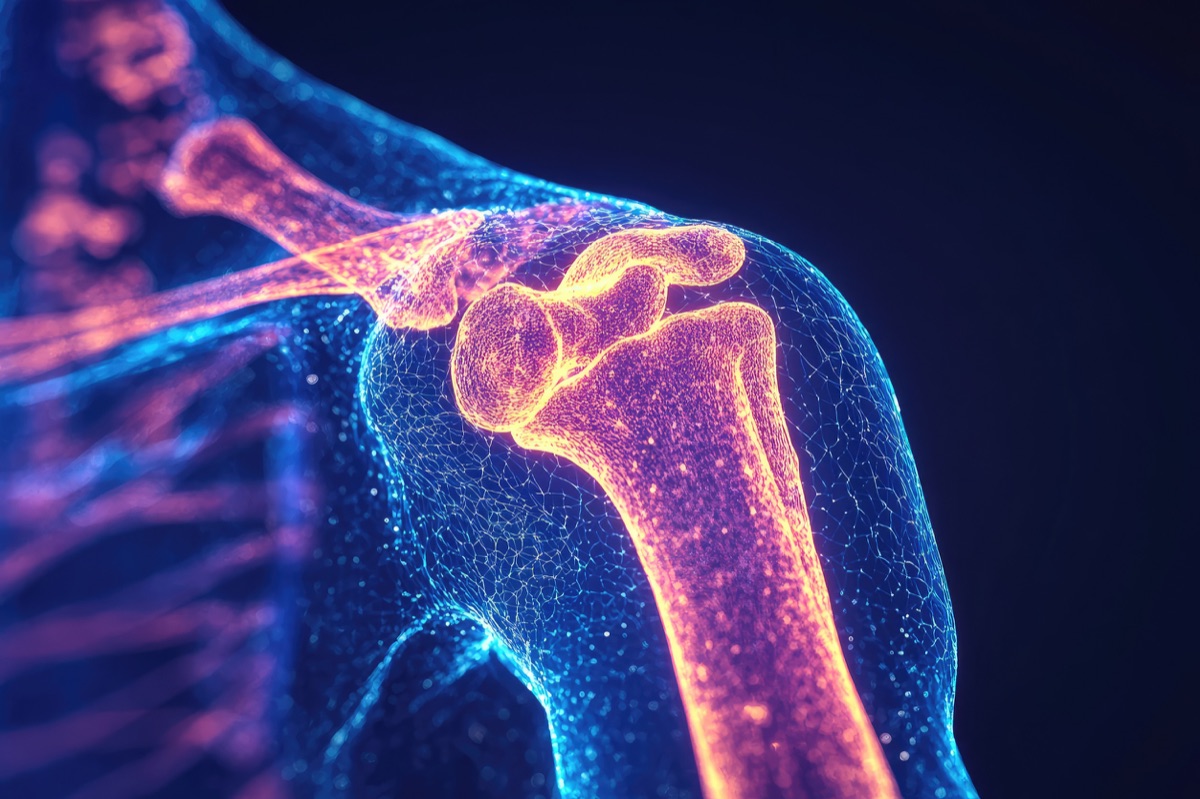

Rotator cuff, frozen shoulder, and impingement. Restore range of motion.